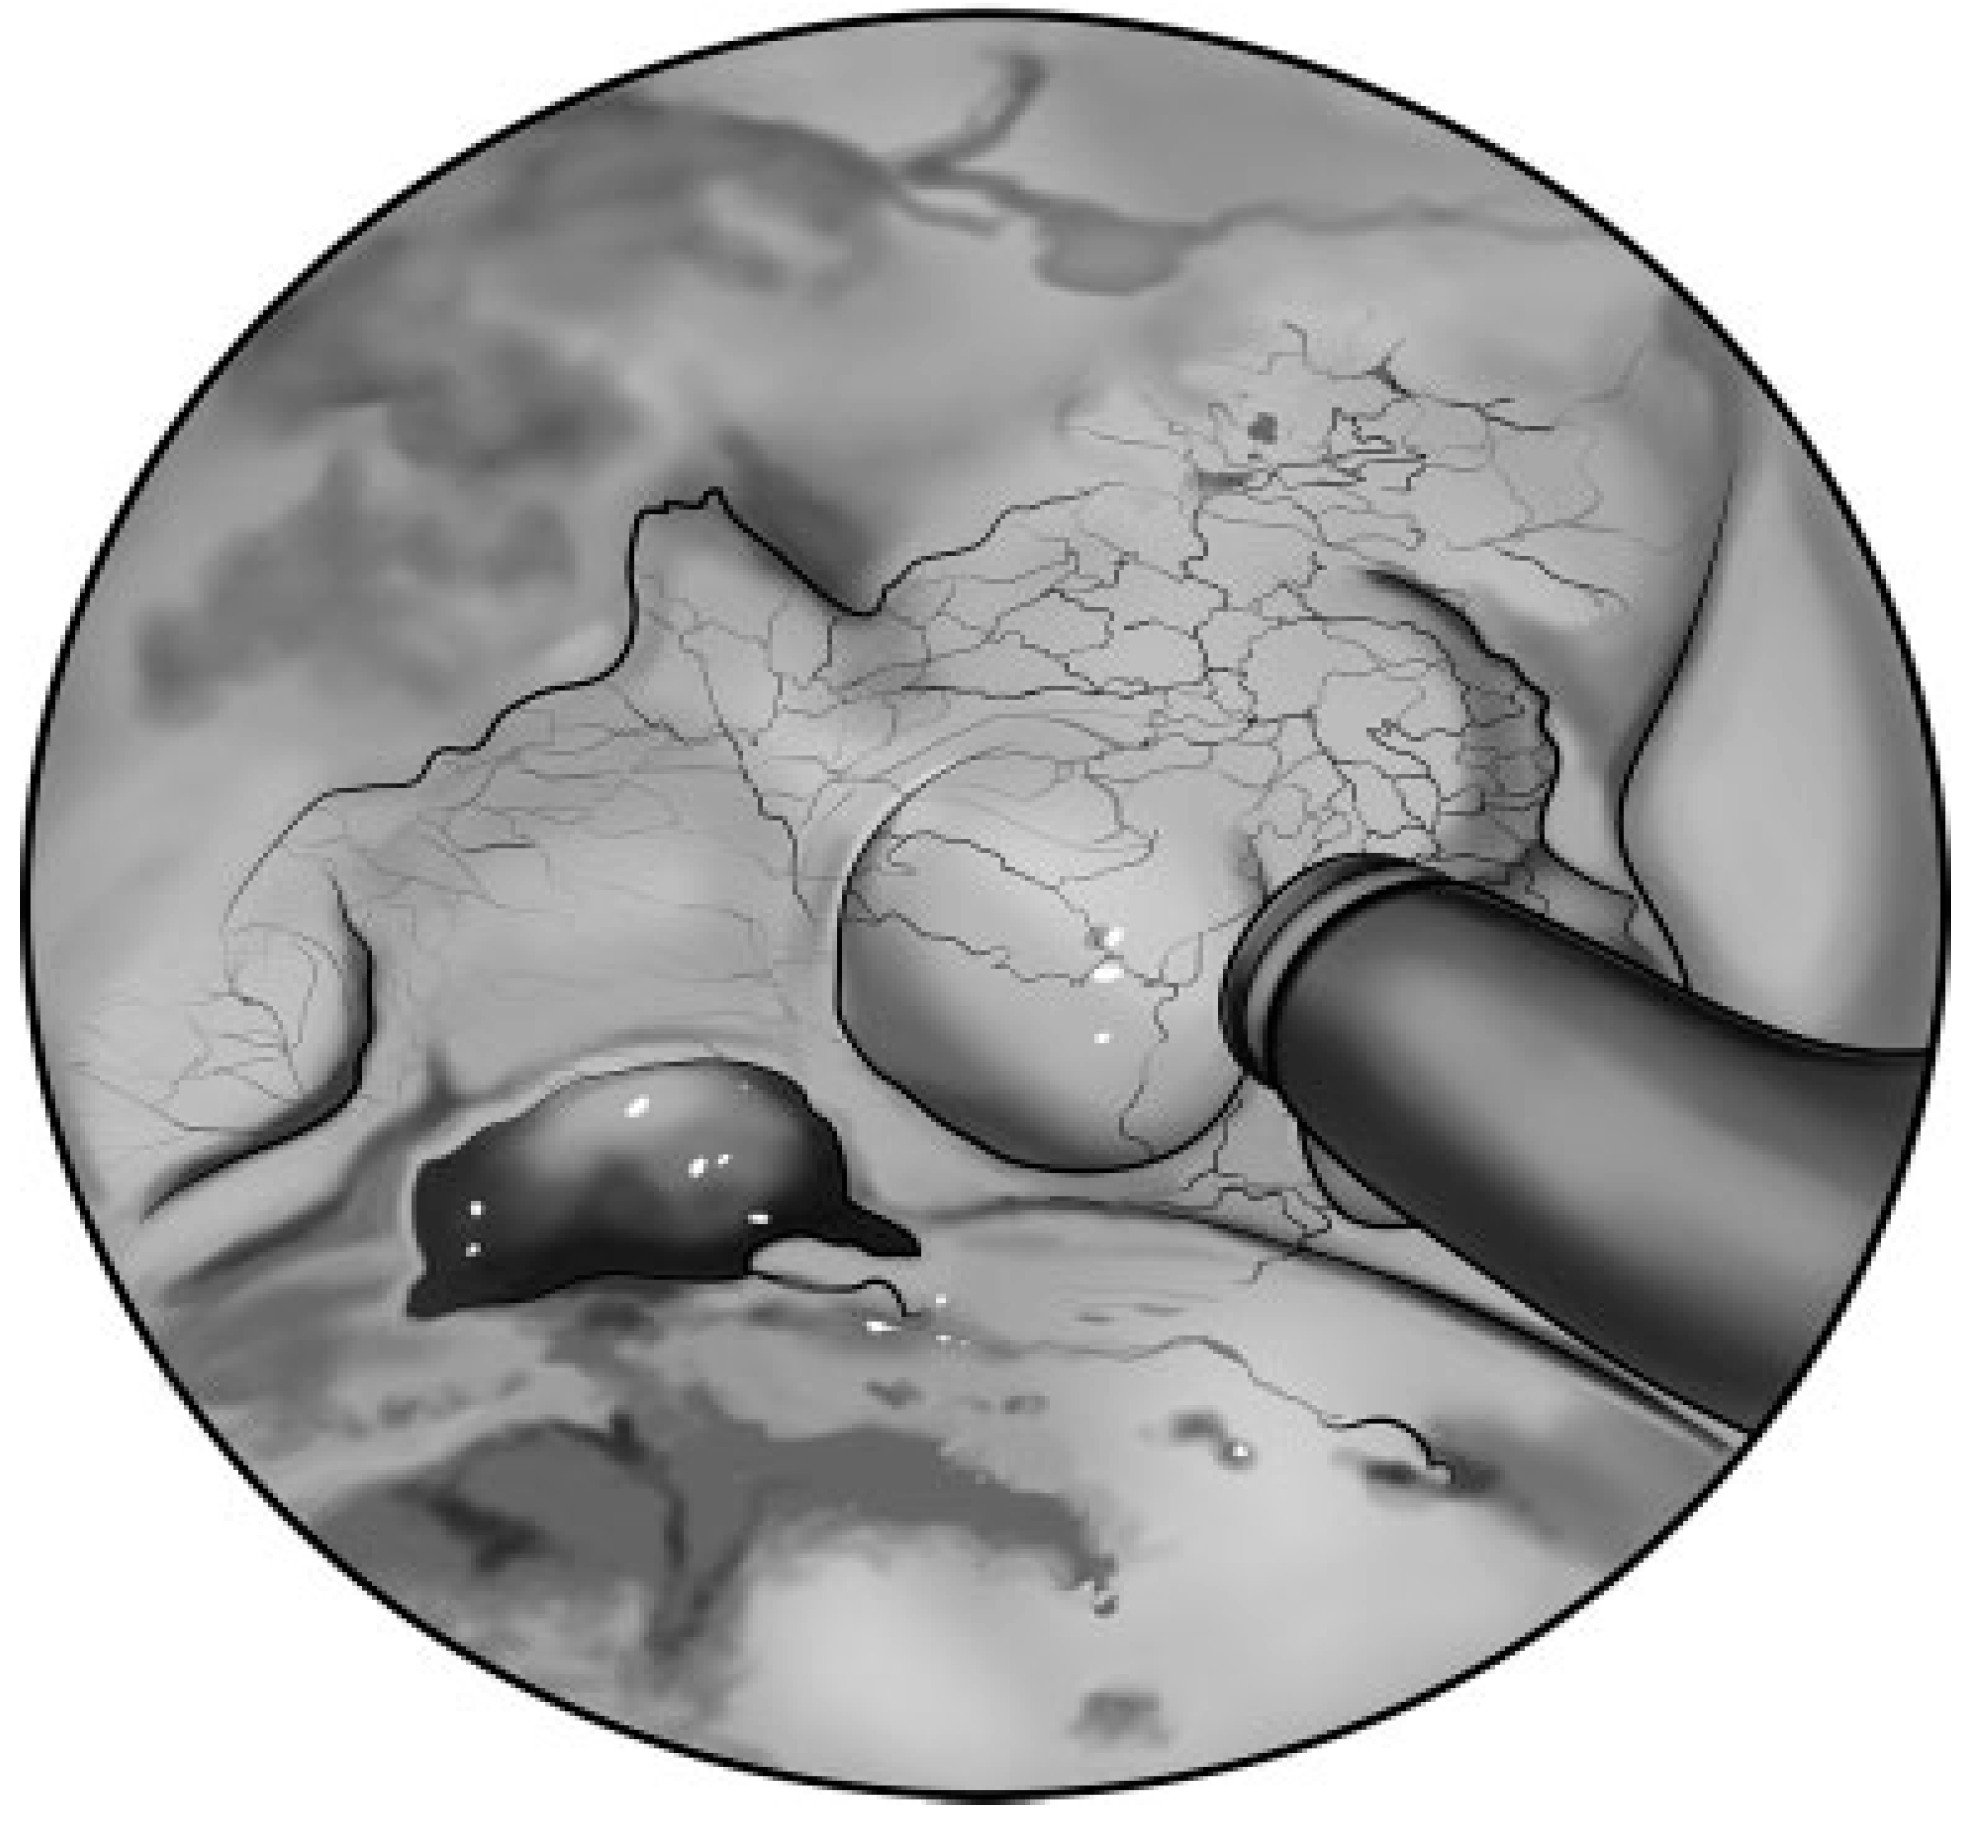

Figure 7.

Intraoperative, endoscopic view of a posterior table frontal sinus fracture with CSF leak. After adequate exposure, the fracture is manually reduced and surrounding mucosa is removed prior to graft placement.